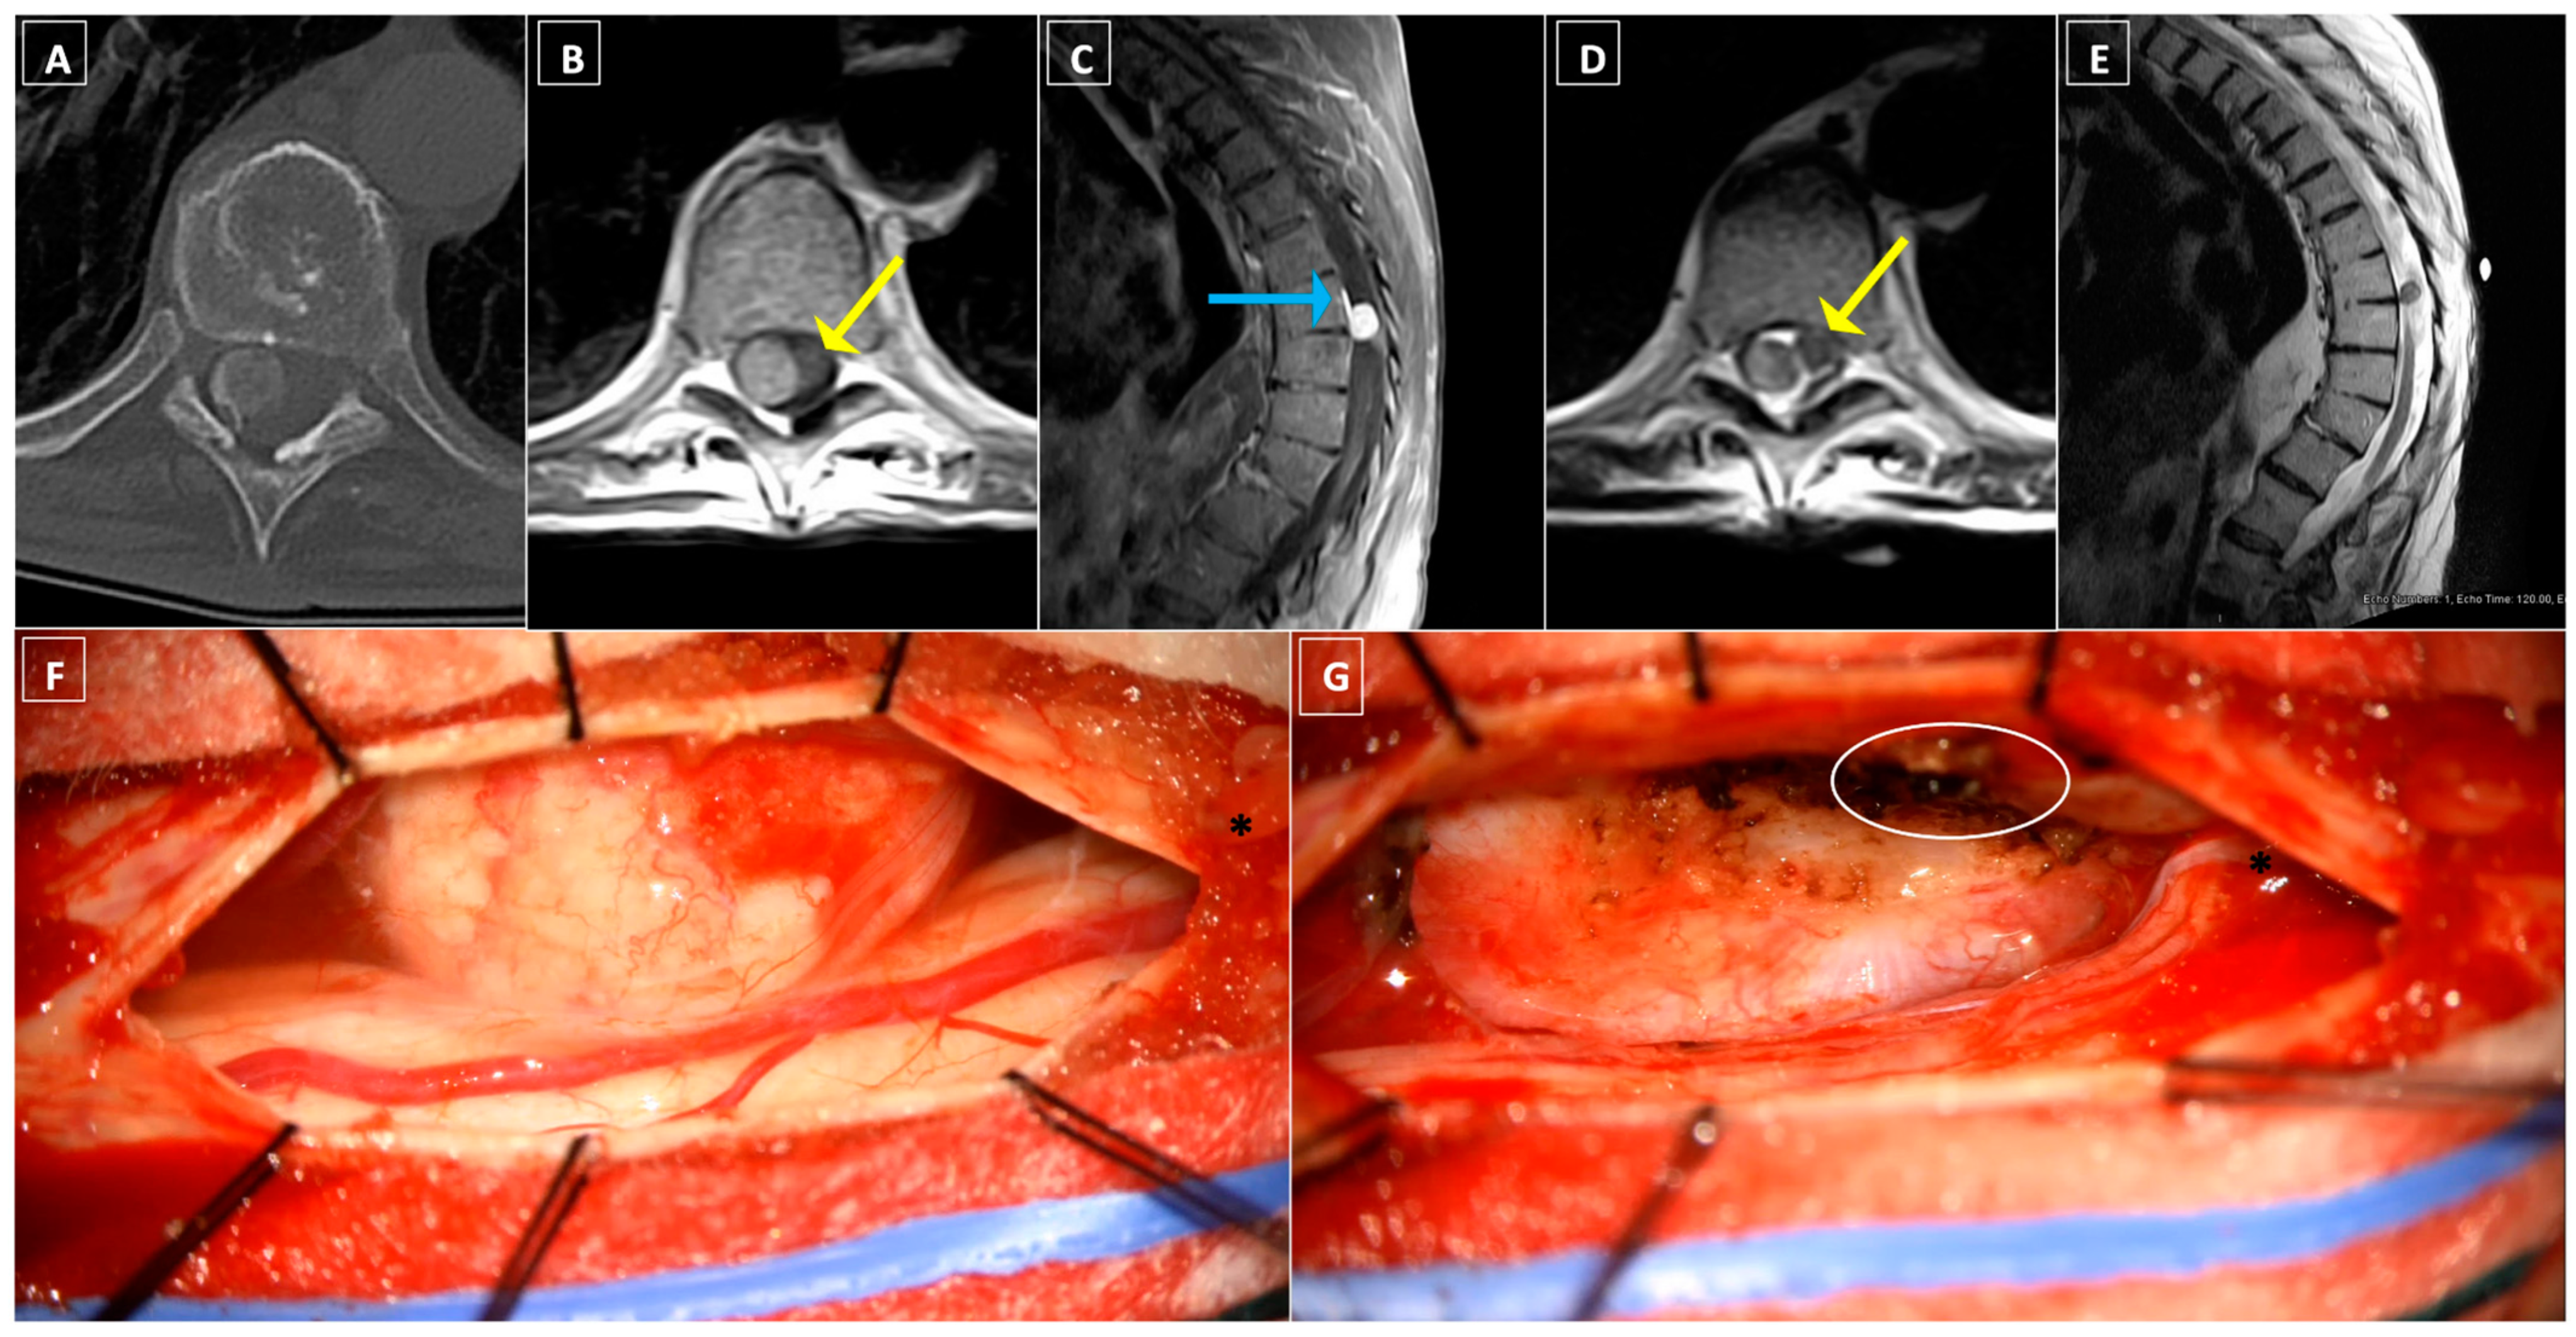

8.2. Case Two: Ventrolateral Cervical Meningioma